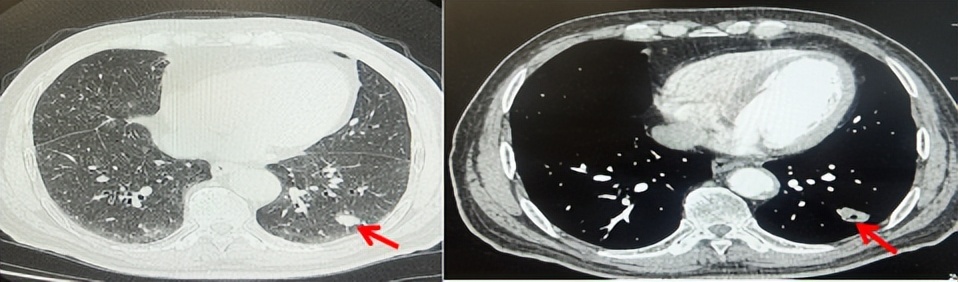

69岁男性,无糖尿病、高血压、心脏病等基础疾病,无吸烟、饮酒史,无肿瘤家族史。2023.06.07行胸部CT检查:右肺上叶胸膜下见肿物影,大小约33mm×22mm,边缘可见分叶,考虑恶性病变可能性大,双肺间质改变(如图1)。2023.06.14行“单孔胸腔镜下右肺上叶切除、肺门及纵隔淋巴结清扫、胸膜粘连松解术”;术后病理:(右肺上叶)腺癌(低分化,实体型占60%,不良腺体占40%),局灶伴神经内分泌标记表达(CD56、Syn),可见STAS及胸膜侵犯,未见确切神经侵犯及脉管内癌栓;(气管切缘)净;(淋巴结)未见转移癌0/26(2组0/2;4组0/6;7组0/2;对侧7组0/8;10组0/2;11组0/3;12组0/2;13组0/1)。术后分期pT2aN0M0 IB期,术后NGS基因检测:无驱动基因突变,PD-L1(22C3)TPS<1%。术后定期复查。

图1:患者手术前(2023.06)胸部CT肺窗及纵隔窗

图2:患者胸膜及肋骨转移(2024.11)胸部CT肺窗、纵隔窗及骨窗

图3:患者免疫联合化疗治疗后胸部CT,(A、B)图展示信迪利单抗联合培美曲塞+卡铂治疗

4周期(2025.02)疗效,(C、D)图展示信迪利单抗+培美曲塞维持治疗6周期(2025.07)疗效